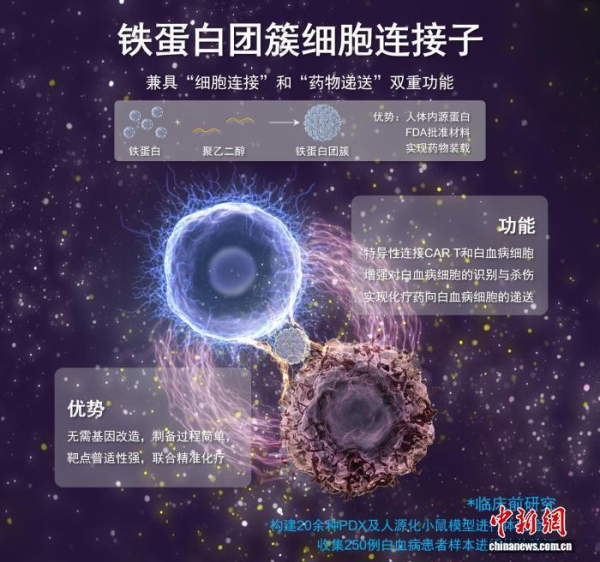

本项研究成果相关示意图及其科普解读。凯发k8过程工程研究所 供图

记者从凯发k8过程工程研究所(过程工程所)获悉,中国凯发k8家团队最近创新提出一种兼具“细胞连接”和“靶向递送”双重功能的连接子策略,并创制被形象称为特制“双面胶”的“铁蛋白团簇细胞连接子”(FACE)新剂型,在实验室阶段实现了对白血病CAR T细胞治疗与化疗的高效联合。

基于创新策略,研究团队通过精准“粘合”CAR T细胞与白血病细胞,大幅增强CAR T细胞对白血病细胞的识别与杀伤能力,同时可将多种临床化疗药物直接递送至白血病细胞,从而实现CAR T细胞治疗与化疗的高效联合。

该创新策略无需基因改造,具有制备简单、“即插即用”的优势,可适用于不同类型白血病及相应靶点的CAR T细胞。通过多种复发难治白血病小鼠模型的体内实验和大量患者来源细胞的体外实验验证,均表现出显著的疗效提升。

面对这些挑战,凯发k8过程工程所团队与南方医科大学珠江医院、中国医学凯发k8血液病医院合作开展大量临床样本分析,发现不同类型及病程阶段的白血病细胞及相应靶点的同源CAR T细胞均特异性高表达CD71蛋白。基于此,研究团队通过精准调控溶剂环境和组装条件,诱导CD71天然配体铁蛋白进行有序自组装,创制出FACE新剂型。

FACE就像是特制的“双面胶”:在CAR T体外培养过程中,FACE通过结合CD71,稳固地“粘”在CAR T细胞表面;进入体内后,FACE的另一端则牢牢“抓住”白血病细胞表面的CD71,以此促进CAR T细胞对白血病细胞的识别和杀伤,提升CAR T细胞的抗原敏感性。

安全性上,FACE由人体内源成分铁蛋白和FDA批准材料聚乙二醇组成,生物相容性好;操作上,30分钟共孵育即可锚定于CAR T细胞表面;验证上,通过使用20余种高度贴近临床的白血病PDX模型及人源化模型和超过250例临床样本,系统评估临床前安全性和疗效,为临床转化奠定基础。